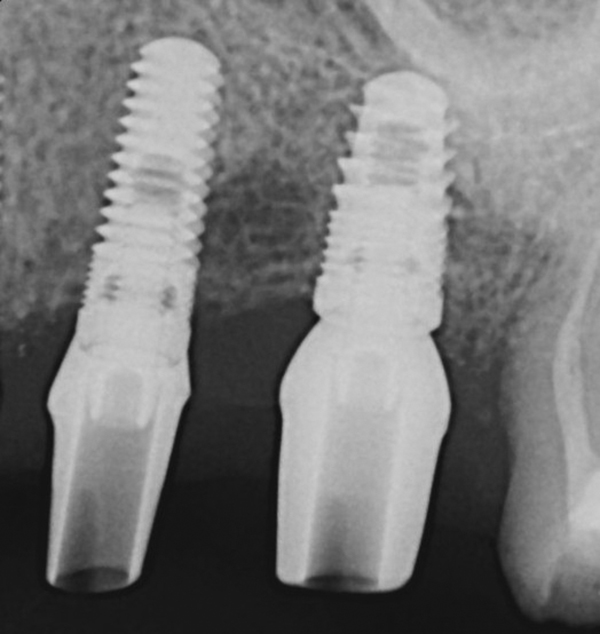

Apparently with time, stable implants placed with low initial torque develop bone characteristics around them that are similar to sites where implants were placed with a high initial torque (Figure 4 and Figure 5). Conversely, for implants placed with a high initial torque, the healing process, despite the high initial torque, provides a level of biologic stability that is not necessarily influenced by the initial insertion torque value.

Fig 4. Clinical view of an implant placed into an immediate extraction socket at site No. 28. A n insertion torque of <10 Ncm resulted in a spinner.

Figure 4

Fig 5. Radiograph of the implant at site No. 28 (shown in Figure 4) with an oversized cover screw, which was used to assist in stabilizing the implant within the osteotomy.

Figure 5